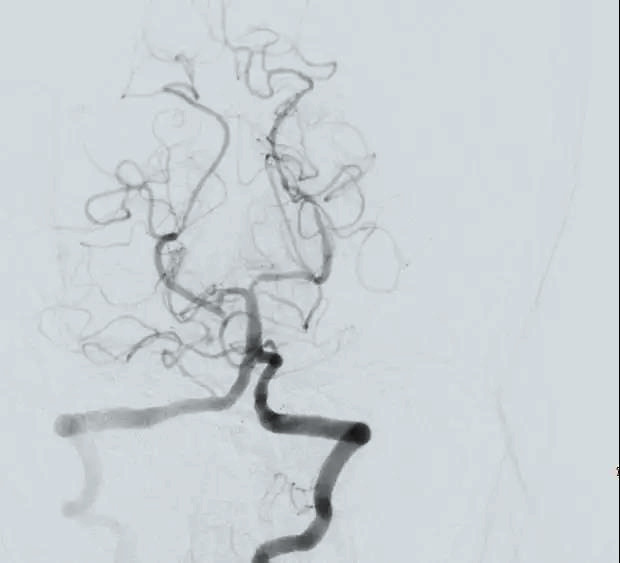

在神經(jīng)外科戴偉民主任的帶領(lǐng)下,李運(yùn)平、劉榮財(cái)醫(yī)生默契配合,團(tuán)隊(duì)協(xié)作為搶救生命爭(zhēng)分奪秒?!叭榧皠?dòng)脈置鞘,基底動(dòng)脈起始部完全閉塞。”腦血管造影再次印證葉女士危在旦夕。“再晚一分鐘,后果不堪設(shè)想!” DSA導(dǎo)管室,一場(chǎng)與時(shí)間賽跑的生命爭(zhēng)奪戰(zhàn)正在進(jìn)行。定點(diǎn)、介入,從放置取栓裝置到送達(dá)栓塞部位,每一個(gè)動(dòng)作都“重若千鈞”,終于在3毫米的動(dòng)脈導(dǎo)管內(nèi)完整取出5X3毫米的血栓,復(fù)查造影,顯示基底動(dòng)脈血流恢復(fù),取栓成功。而此時(shí),距離葉女士抵達(dá)DSA導(dǎo)管室,僅僅過(guò)去了20分鐘。

取栓前